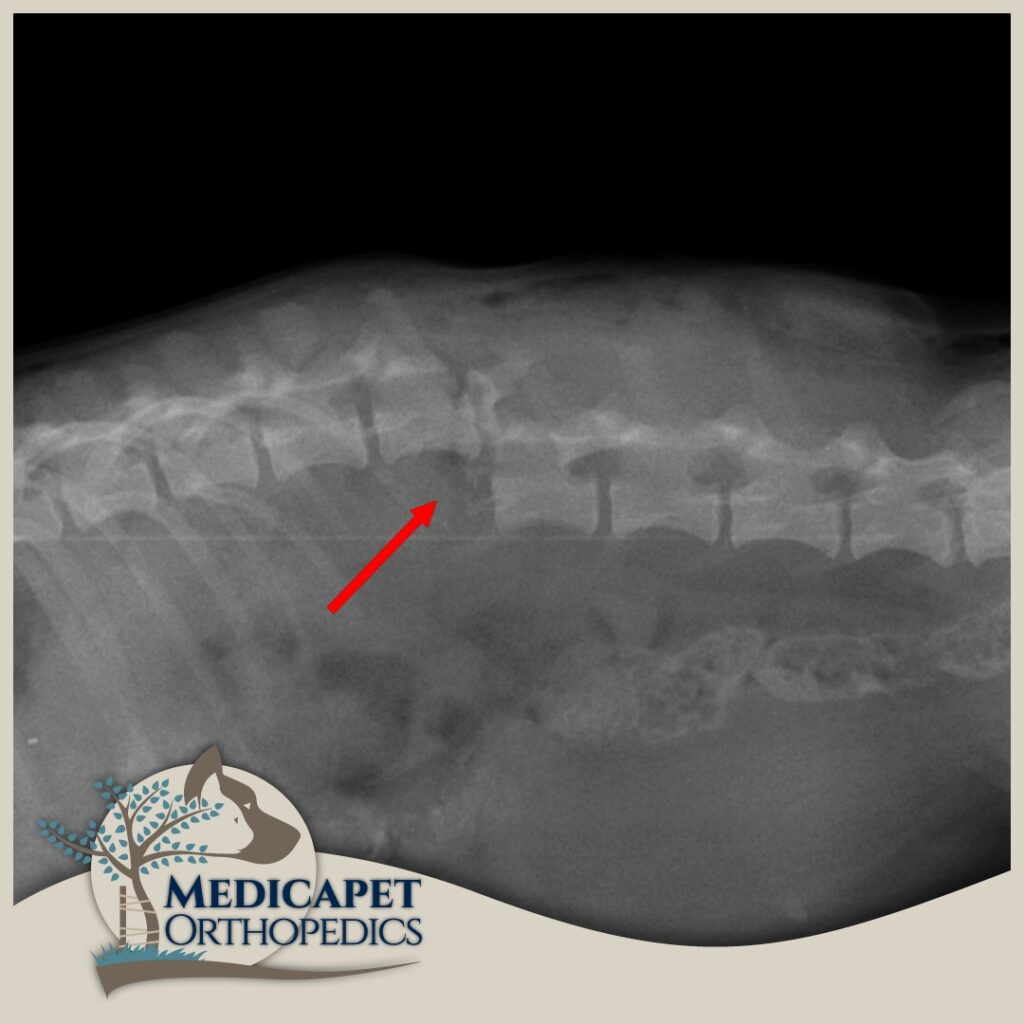

omurga cerrahisi

omurga kırıkları, disk fıtığı gibi olgularda acil müdahale başarı şansını yüksetir.

zaman geçtikçe kalıcı felç olasılığı artar.

zaman geçirmeden bize ulaşın

Kemik dokuların içinde bulunan veya kemik dokulara paralel seyreden sinir sistemi organlarının hasarları bu kemik dokuların hasarına bağlı olarak gelişebilirler. Yumuşak kıvamlı olan sinir dokuları en küçük travmaya karşı oldukça duyarlı olup, yeterli beslenme ve korunmaya ihtiyaç gösterirler. Bu sistemi oluşturan organlardan bazıları dış ortama karşı kafatası ve omurga gibi kemikten örtülerle korunur. Bu sebeple sinir dokuya komşu ya da onu içinde bulunduran kemik dokunun tedavi ve onarımı çok önemlidir ve özenle uygulanmalıdır. Öte yandan sinir dokuya komşu olan kemik dokunun tedavisi sırasında sinir dokuya zarar

verilmeden tedavinin ya da operasyonun yapılması da büyük önem taşımaktadır. Keza sinir dokuların, kemik dokudan bağımsız bazı hastalıklarında da (tümörler

vb.) kemik dokuya müdahale gerekeceğinden Nöroloji ve ortopedi dalları birbiri ile yakından ilgilidir.

Kliniğimizde karşımıza çıkan sinir sistemi hasarlı hastaların pek çoğu bu hasarı bazı kazalar

sonucunda almış olarak geliyorlar. Trafik kazaları, yüksekten düşmeler, insan saldırısı, başka bir

hayvanın saldırısı gibi olayların sonucunda özellikle omurgada kırıklar, kırık bulunmayan omurga

travmaları, kafatası hasarları, kol – bacak ve kalça kırıklarına bağlı geçici ya da kalıcı felç durumları

gibi durumlar en sık tedavi ve opere ettiklerimizin başında geliyor. Öte yandan bazı ırkların genetik

yatkınlıkları da omurga problemlerine yol açabiliyor.